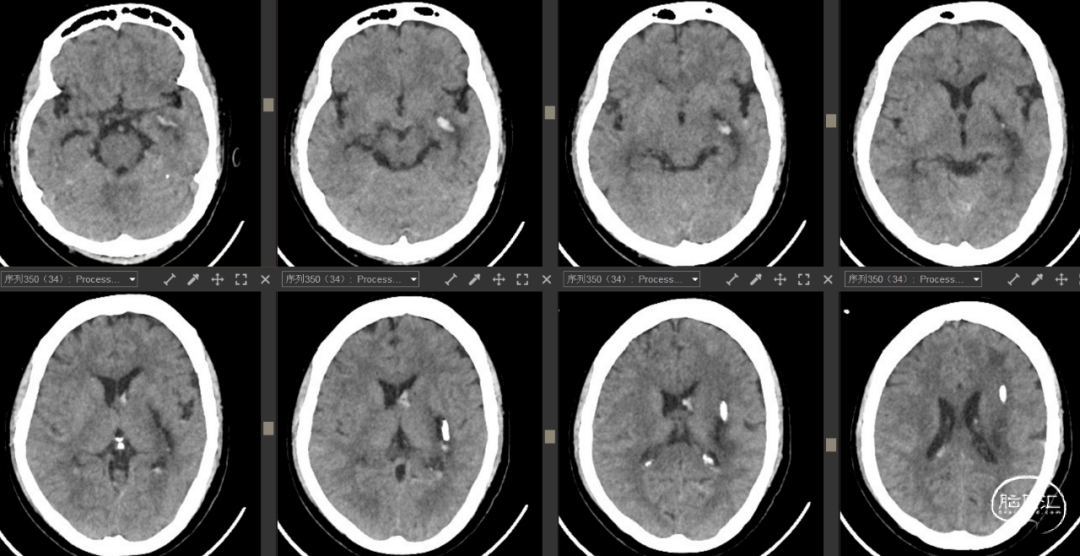

患者阳某,女,65岁,因“头晕伴左侧肢体乏力1.5小时”入院2023-07-31入院。

查体:神志嗜睡,GCS评分13分(E3V5M5),呼唤睁眼,无失语,对答切题,构音含糊,双瞳孔等圆等大,直径为2.5mm,张口及伸舌检查不配合,左侧肢体肌力0级,右侧上下肢体5级,四肢肌张力正常。左侧巴氏征(+)。

检查:2023年7月31日急诊头颅CT提示:右侧丘脑出血破入右侧脑室。

既往发现有“高血压”,未规范服药治疗;2年前胰腺手术史,具体不详。

诊断:

1. 右侧丘脑出血破入脑室

2. 高血压病3级(极高危)

术前讨论及手术指征:出血量虽然不多但血肿破入侧脑室引起意识障碍、肢体肌力0级。丘脑血肿压迫静脉以及分泌含铁血黄素可导致进一步水肿损害脑组织的可能,建议尽早排除血肿有减残的可能性。家属经过商议后积极要求微创术式。

手术方案:经颞叶入路机器人辅助导航右侧丘脑血肿穿刺引流。

![]()

2023年7月31日

![]()

术后3天CT